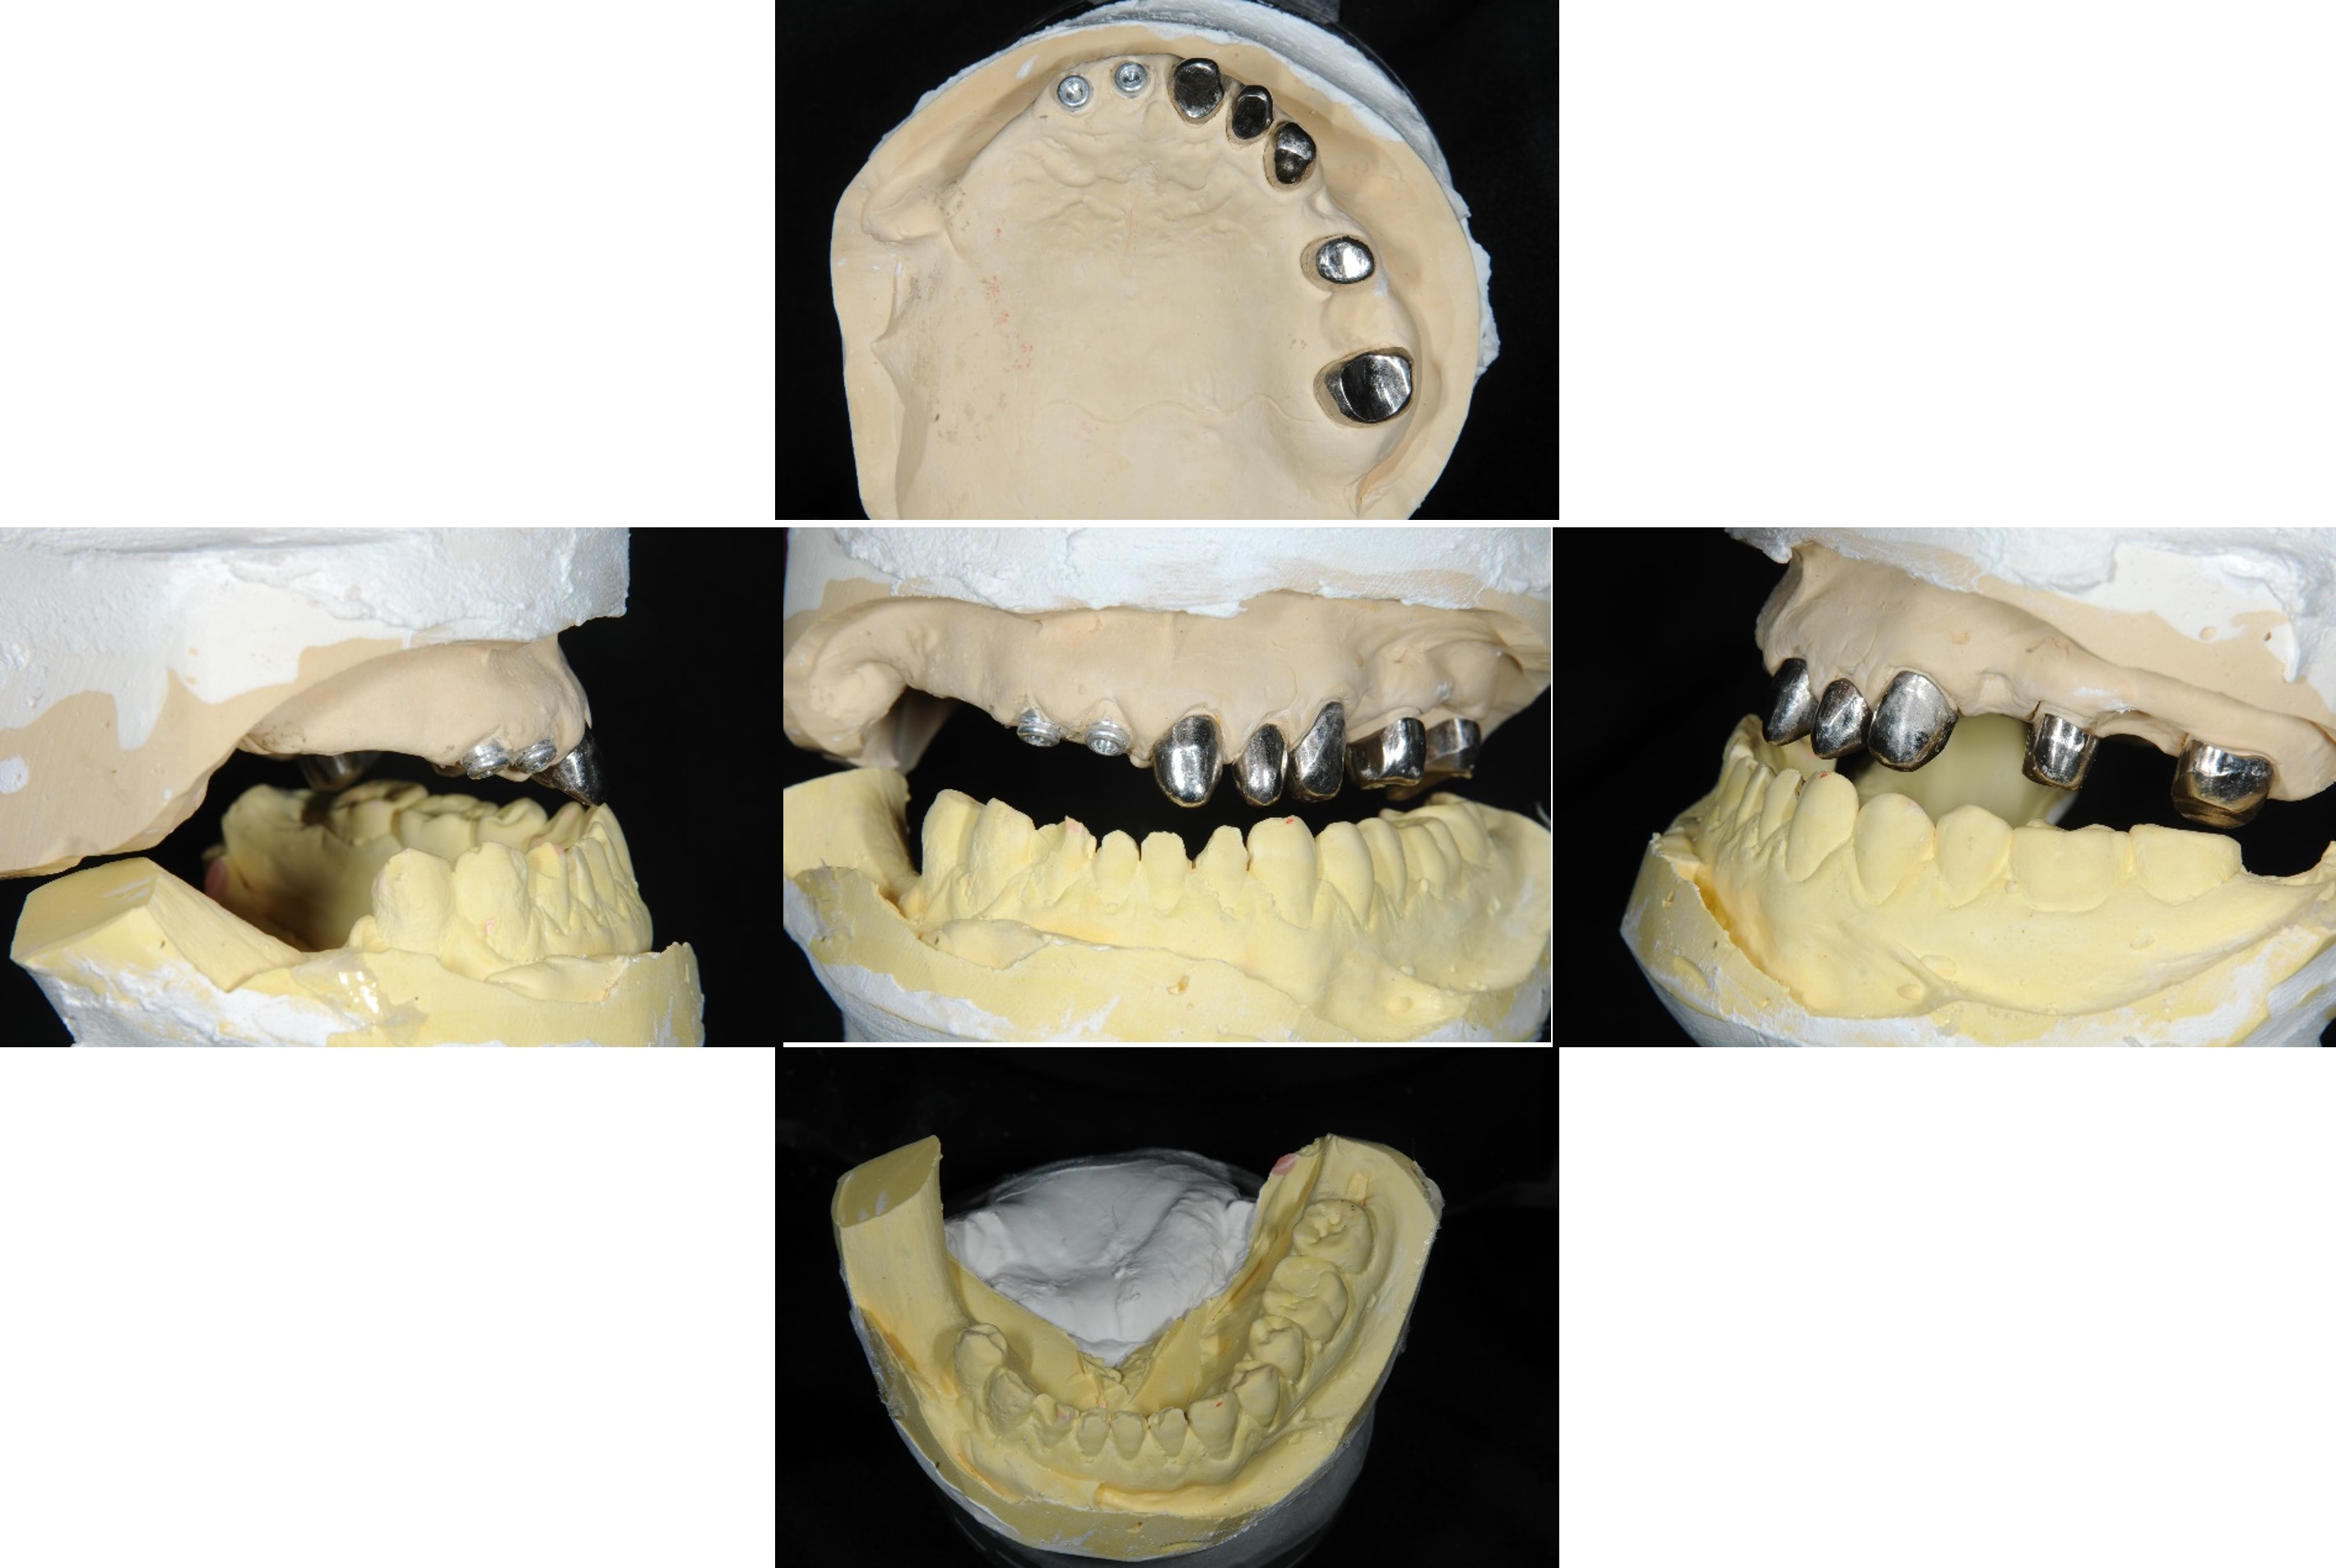

內冠套件

蠟牙製作

組合後外冠及活假牙套件

外冠及活動假牙套件

活動假牙套件